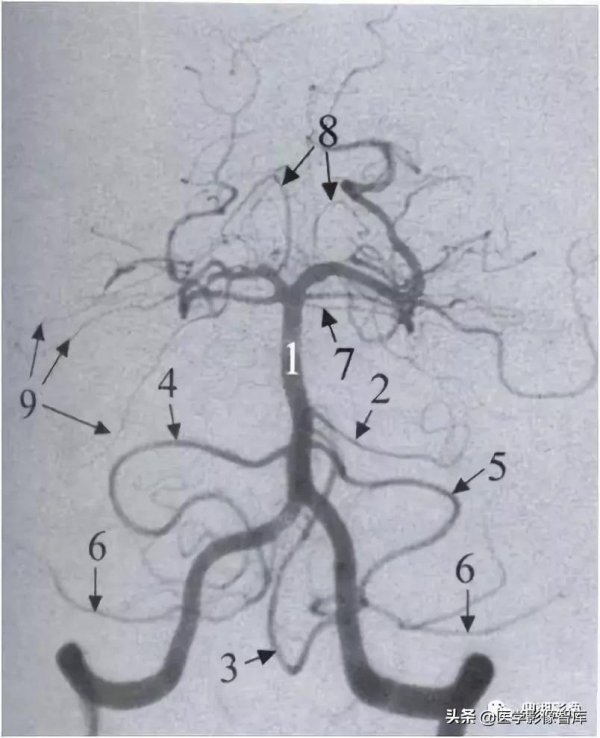

椎基底動脈系統及其分支解剖(前後位):

1.右椎動脈 2.左椎動脈 3.脊髓前動脈 4.小腦後下動脈(PICA)

5.基底動脈 6.小腦前下動脈(AICA) 7.腦橋外側支

8.小腦上動脈(SCA) 9.大腦後動脈 10.後交通動脈 11.頸內動脈